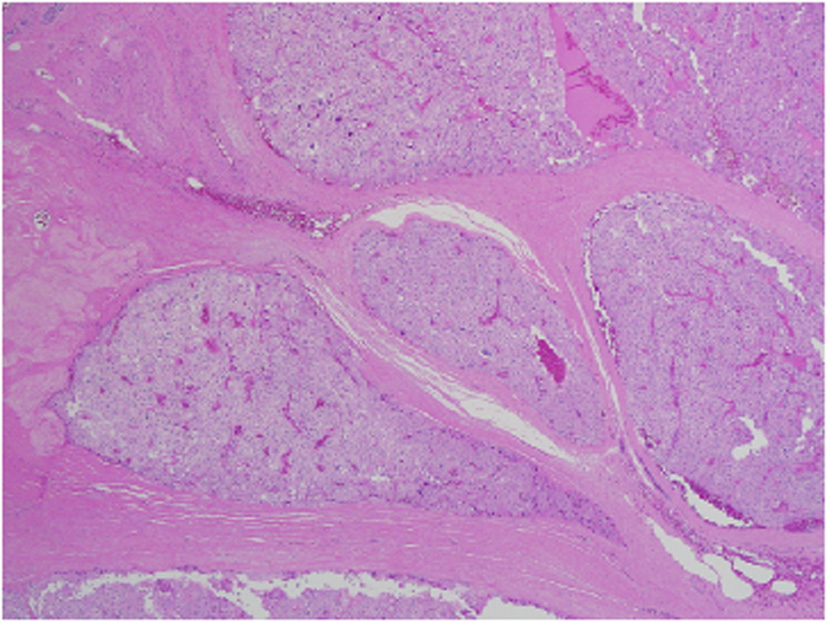

Architecturally, the lesion shows a solid to trabecular growth pattern and is associated with hemorrhage and hemosiderin deposition (Fig. 4). In addition, there are foci highly suspicious for lymph-vascular invasion, and the lesion appears to be poorly encapsulated, with islands of tumor separated by thick fibrous bands (Fig. 5). Morphologically, the cytoplasm is clear to amphophilic, with prominent and distinct cell borders. The background cells have monotonous nuclei with neuroendocrine “salt and pepper” chromatin (Fig. 6). The cells of concern range from moderately pleomorphic to wildly atypical and have irregular nuclear contours. In many areas multinucleation is identified. The nucleoli range from inconspicuous to prominent with cherry-red eosinophilia, irregular membranes and peri-nucleolar halos, the latter being a feature almost exclusively seen in PCA [12] (Fig. 7). The sum total of these findings supports a diagnosis of intrathyroidal parathyroid carcinoma (Fig. 8, 9). In this case, the hypercellular parathyroid tissue noted in several of the sections is morphologically distinct from the predominant neoplasm, interpreted as carcinoma (Fig. 9).

![]() Click for large image | Figure 4. Low power view of parathyroid carcinoma highlighting thick surrounding and intersecting fibrous bands. |